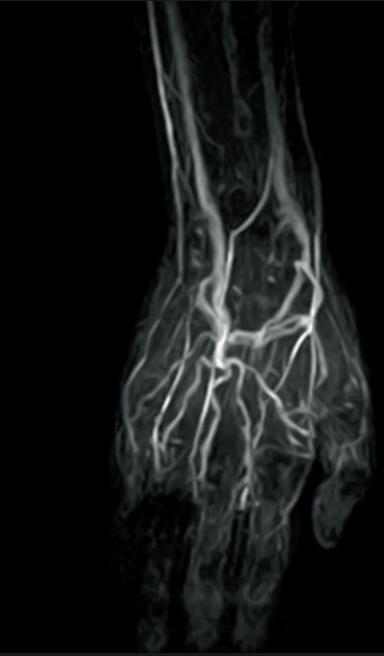

3D-TOF VR image